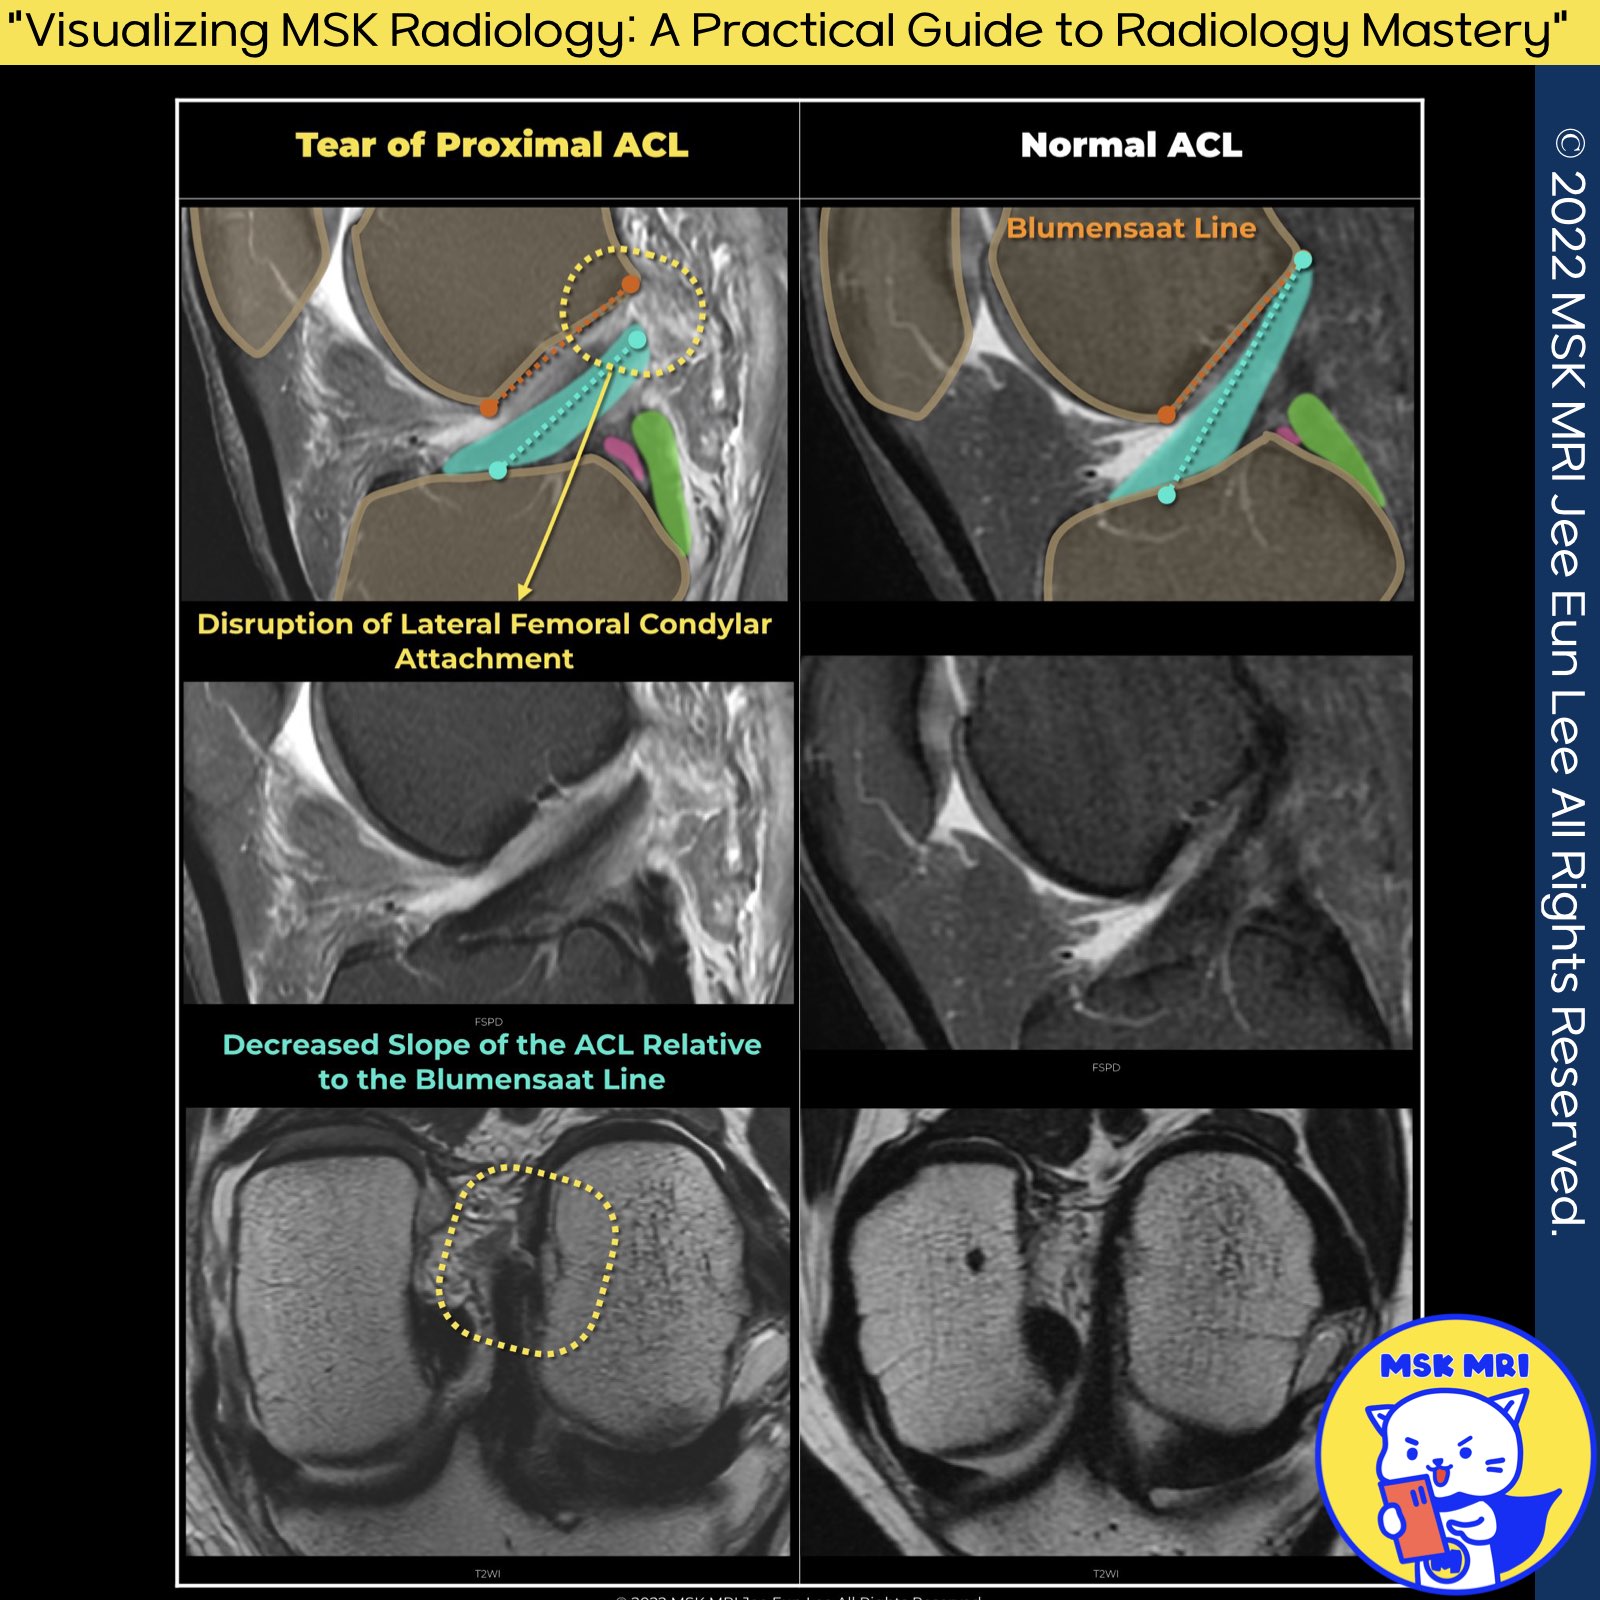

✅ Normal ACL vs. ACL Tear at Femoral Insertion

- Normal ACL:

Appears as an elliptical, homogeneous low signal on axial MRI images, indicating a firm attachment to the lateral femoral condyle. - ACL Tear at Femoral Insertion:

- Axial MRI: Shows increased signal within the proximal ACL fibers or fluid between the torn ACL and lateral femoral condyle, suggesting a tear.

- T2-Weighted Imaging: High signal intensity within the ACL and fluid presence are key indicators of a femoral attachment tear coronal images.